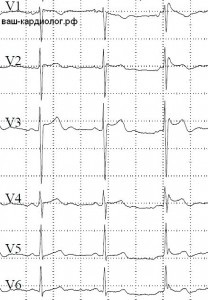

Képek channelopathiák EKG (elektromos szívbetegségek primer)

↓ Brugada szindróma nyereg-back (nyereg-alakú) formában. Jellemző változás a jobb mellkasi vezet.

↓ Brugada szindróma. Egy egység (jobb) „teljes» coved-komplexum.

↓ szindróma megnyúlt QT. Nem sokkal a meghosszabbítás (540 ms, amelynek mértéke a 470 ms Holter), de ez van. És a T hullám után hullám S V4-V6 vezet látható, hogy vizuálisan több hosszúkás QT.